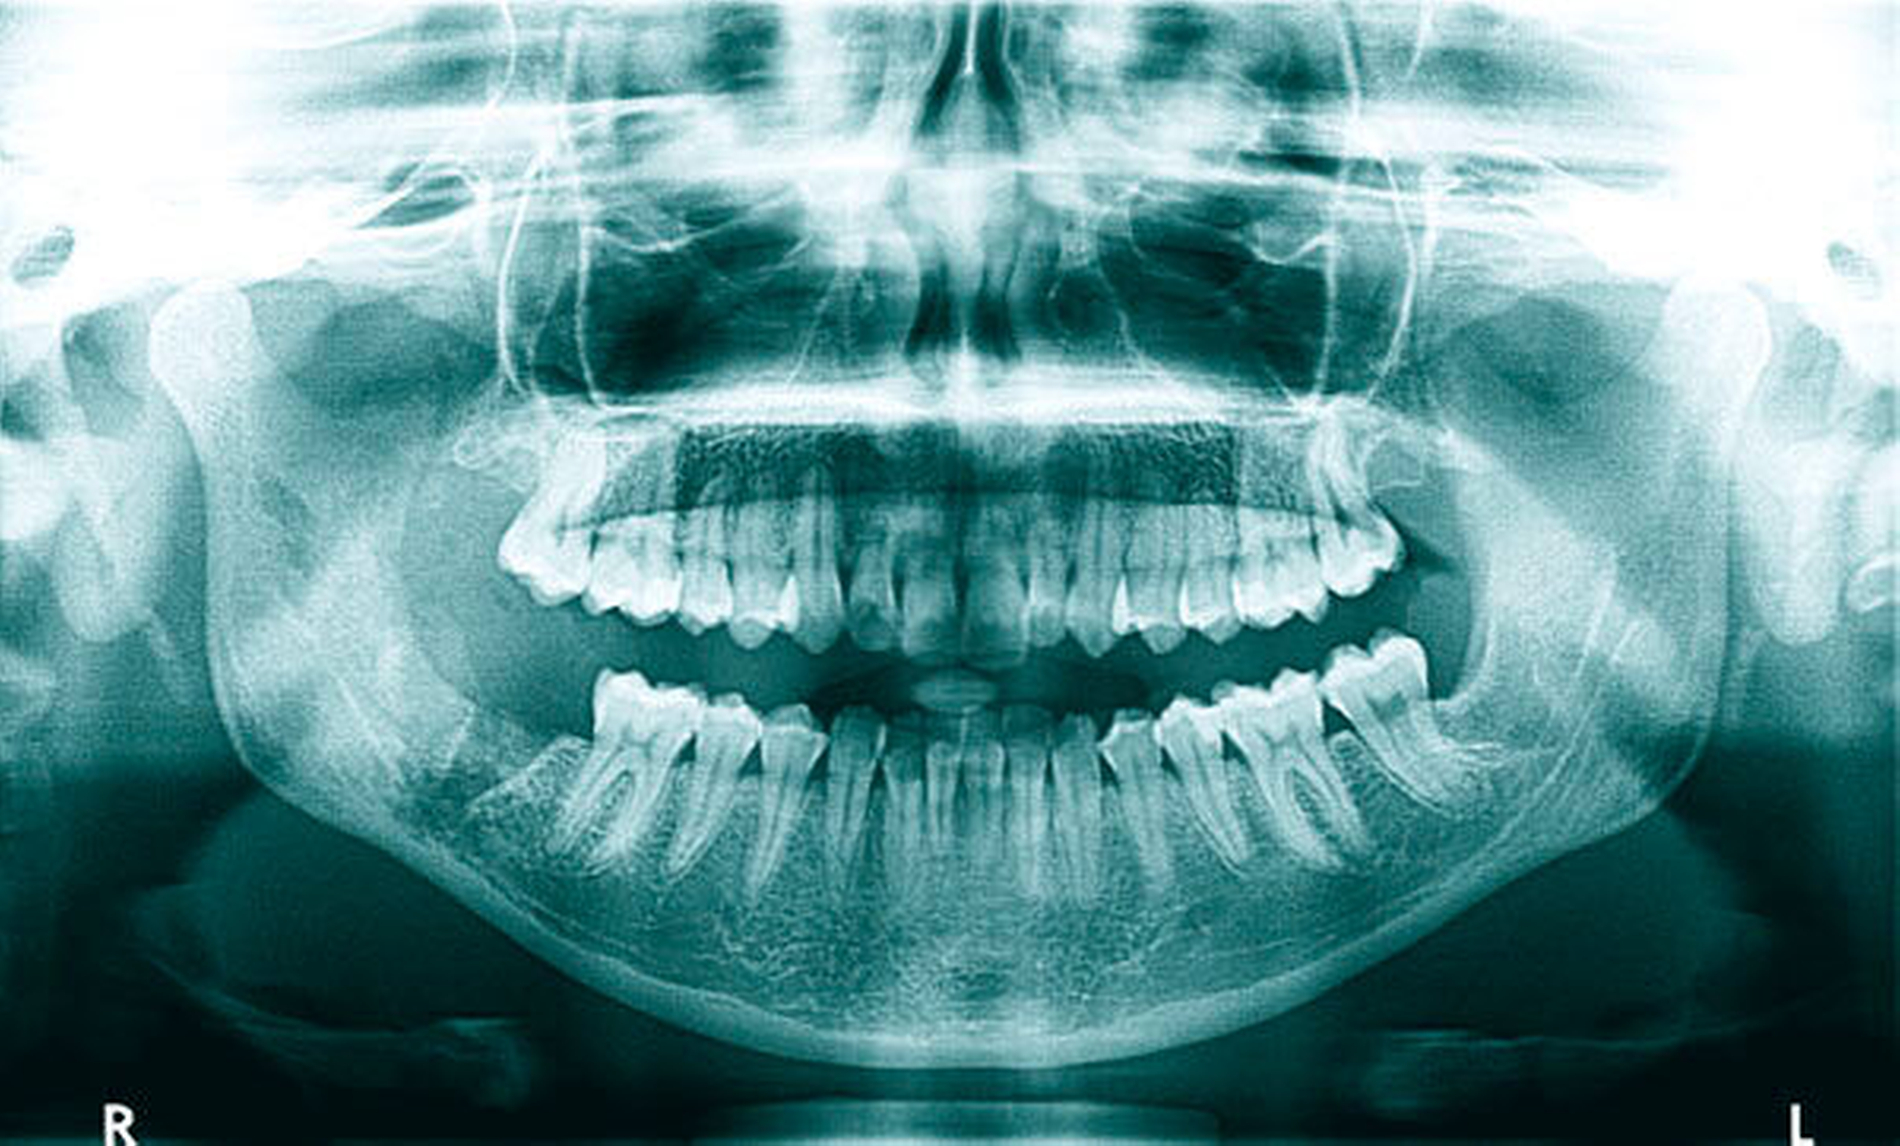

Im weiteren Verlauf von 2016 bis Anfang 2017 erfolgten aufgrund rezidivierender Beschwerden eine hyperbare Sauerstofftherapie (HBO) in der Uniklinik in Düsseldorf und auch eine weitere Dekortikation in der MKG-Abteilung der Kollegen. Die regelmäßigen OPG-Kontrollen in der Zeit zeigten eine sklerosierende Osteomyelitis beziehungsweise eine Sklerosierung der Mandibula (Abbildung 5).